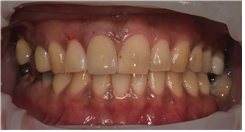

치료 후